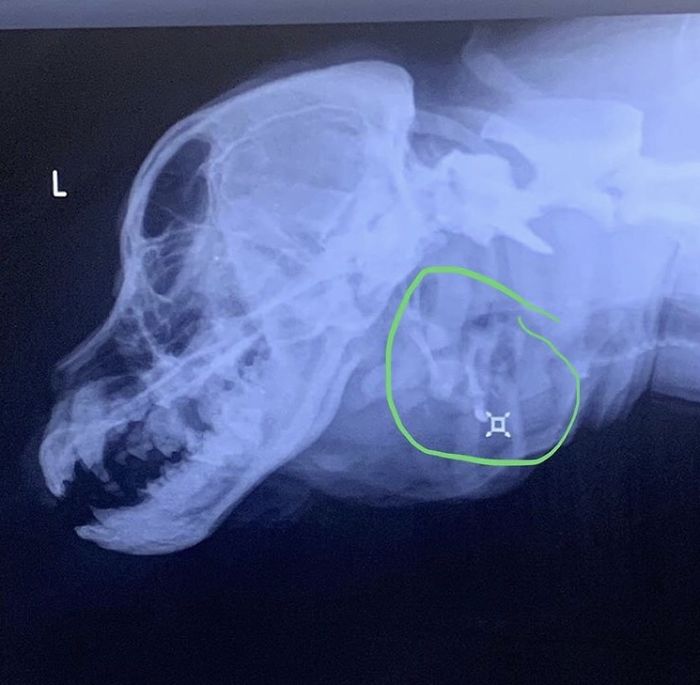

The 2nd mouth does not have any jaw so it cannot chew anything. It still produces saliva and is also connected with the original mouth. The extra mouth has three teeth which are cleaned by a vet often.

Despite her deformity, Toad is a healthy and sweet dog. Her X-rays also do not show any serious condition. The theory is that in the womb she might have absorbed one of her twins.